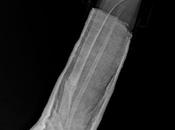

Ractura a nivel distal de tibia y peroné en fases de consolidación, las cuales...

AP Y LATERAL DE TIBIA Y PERONE LA PROYECCIONES RADIOLOGICAS OBTENIDAS NOS MUESTRAN LOS SIGUIENTES HALLAZGOS: -Tejidos blandos, con presencia de material de... Leer el resto